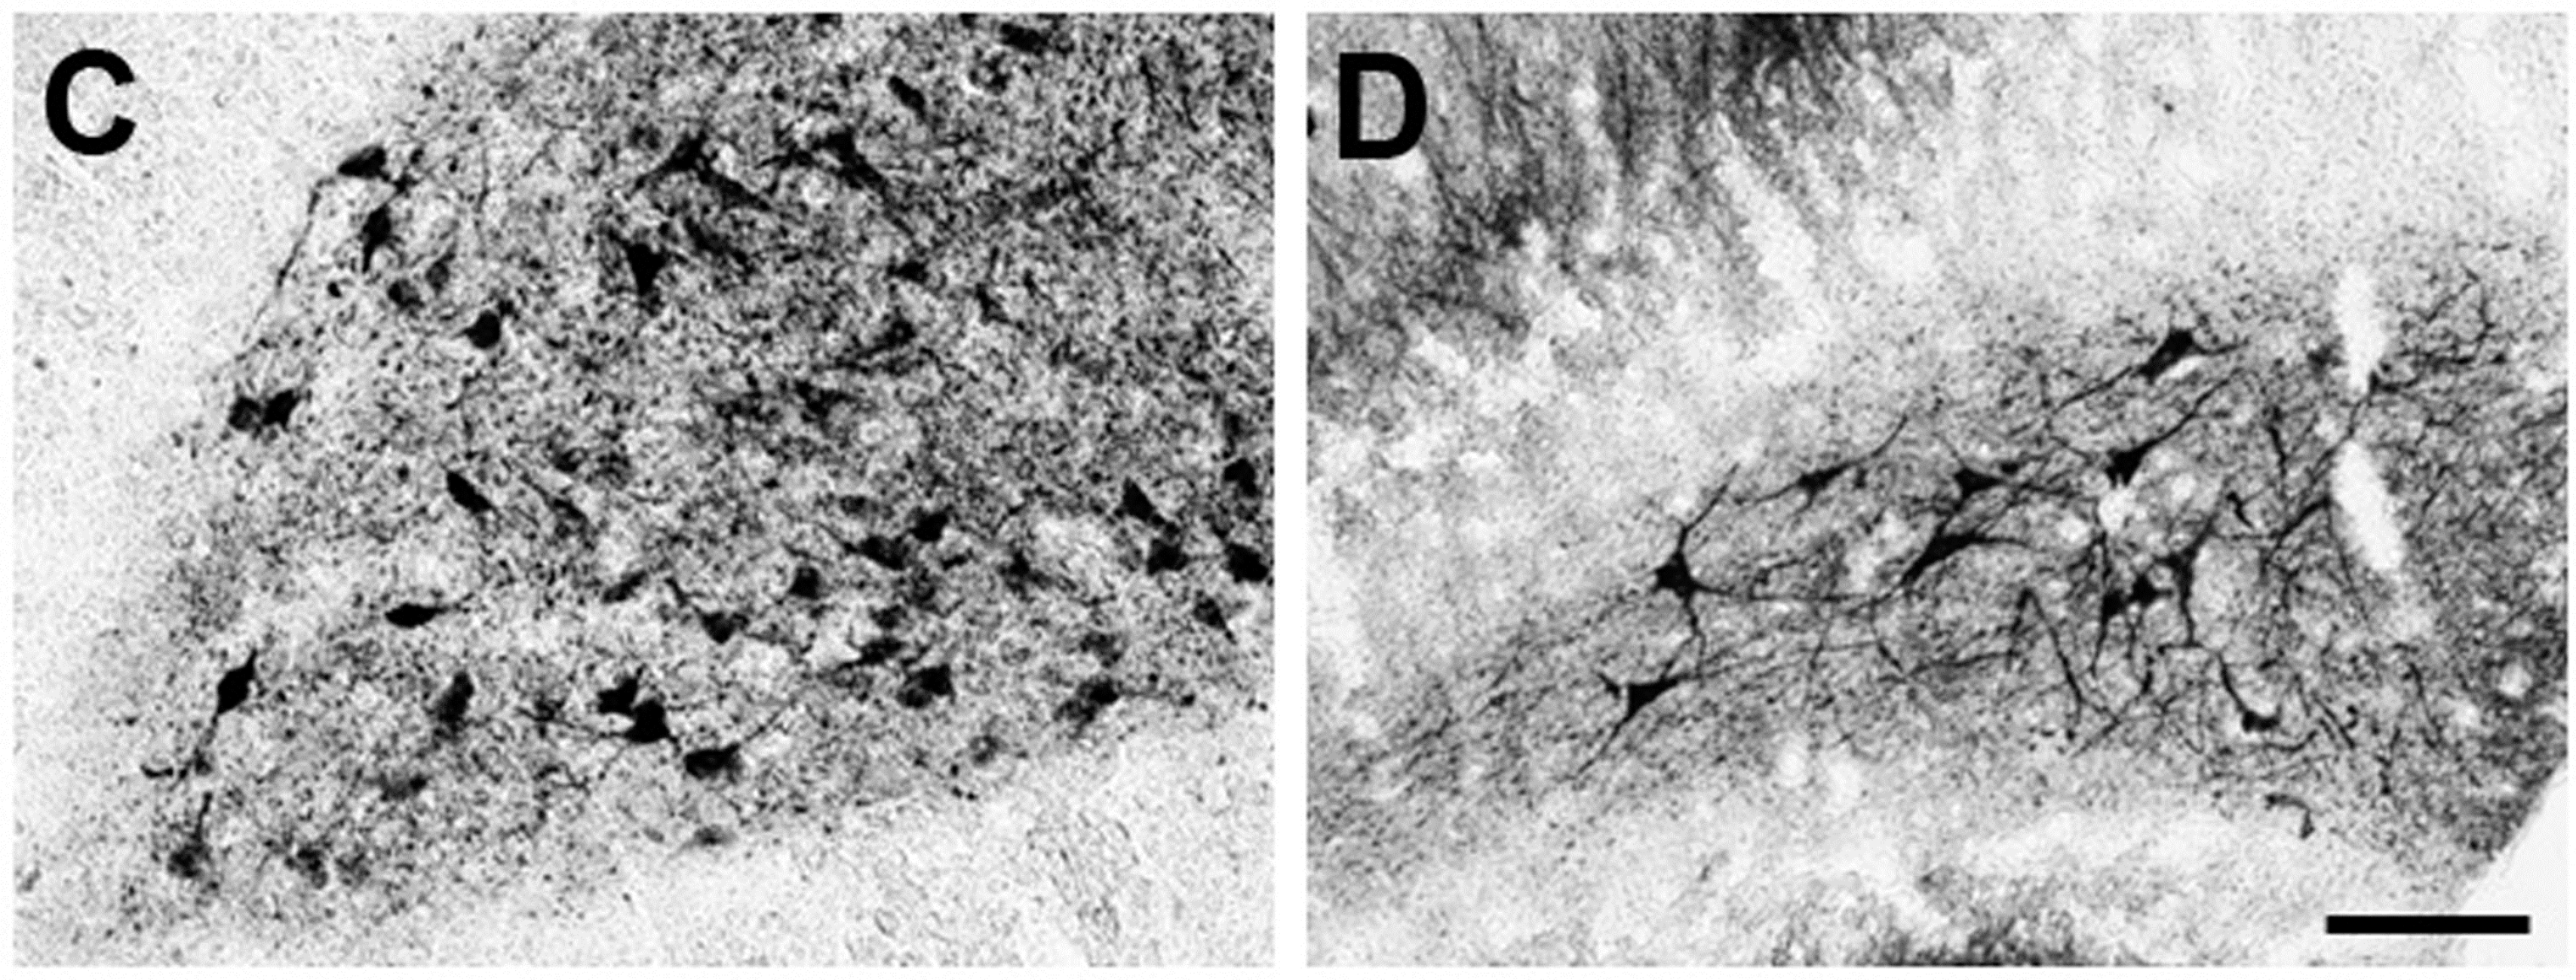

- Dominguez-Alonso, A.; Ramirez-Rodriguez, G.; Benitez-King, G. Melatonin increases dendritogenesis in the hilus of hippocampal organotypic cultures. J. Pineal Res. 2012, 52, 427–436. [Google Scholar] [CrossRef] [PubMed]